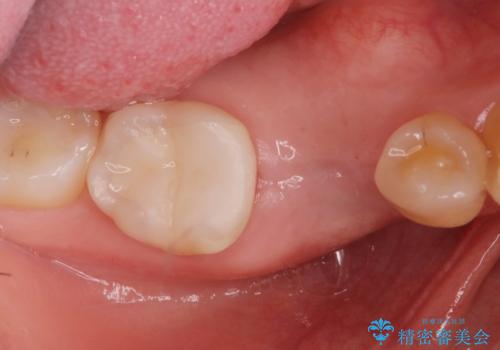

併用して銀歯も気になるとの事でしたのでセラミック治療も行いました。

- インプラント体、アバット、仮歯、ジルコニアクラウン・42.9万円 e-maxインレー・7.7万円 費用は治療当時の料金となります

適合の良いセラミックが入りました。